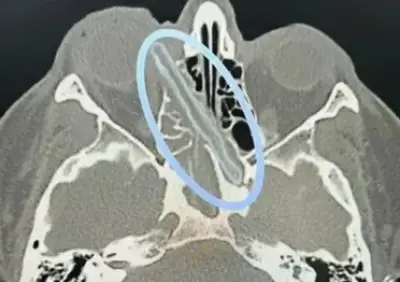

تطلبت الحالة الطبية تدخلاً جراحياً عاجلاً بسبب تشخيص ورم دماغي خطير لدى المريضة، التي كانت في مرحلة متقدمة من الحمل. شكلت العملية تحدياً كبيراً للفريق الطبي، حيث كان من الضروري إزالة الورم بالكامل مع ضمان عدم تعريض حياة الجنين لأي مخاطر.

استخدم الأطباء تقنيات جراحية متطورة وأجهزة مراقبة دقيقة خلال العملية، التي استمرت لعدة ساعات. تم التخطيط للعملية بعناية فائقة، مع مشاركة أخصائيين في جراحة الأعصاب والتخدير وطب النساء والتوليد، لضمان تحقيق أفضل النتائج.

أعلنت مدينة الملك سلمان الطبية أن العملية جرت بنجاح تام، حيث تم استئصال الورم الدماغي بالكامل دون أي مضاعفات. كما تم الحفاظ على سلامة الجنين طوال فترة التدخل الجراحي، مما يعكس الكفاءة العالية للفريق الطبي والبنية التحتية المتطورة للمستشفى.